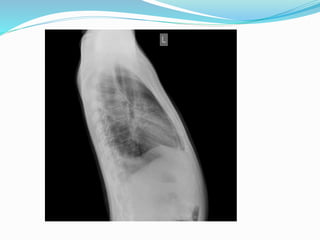

CXR

Chest X ray

 Pulmonary venous congestion and pleural effusions (late in

the disease).

 Calcified pericardium is highly suggestive of CP when present

in a patient with constrictive/restrictive physiology.

 Chest Radiography

 Findings are commonly unremarkable.

 Severe pericardial calcification (20-30%).

 If no significant pericardial effusion - cardiac silhouette may

appear normal.

 The superior vena cava may be dilated.

 Pleural effusions are common (late), usually bilateral.

Posterior-anterior and lateral chest radiograph demonstrating a

thickened calcified pericardium in another patient with CP